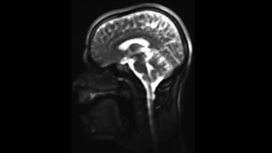

Rapping in an MRI scanner

Take a look inside Alex Lathbridge’s vocal cords a rap performance.